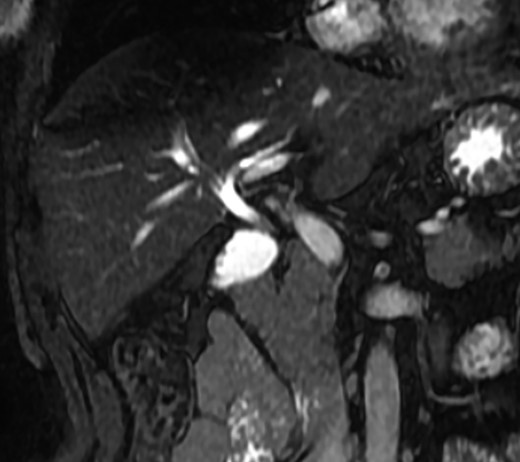

A magnetic resonance cholangiopancreatography (MRCP) confirmed the absence of gallbladder and of the cystic duct and artery (Figs 4–6). No other abdominal anomaly was identified.

MRCP showing biliary tract with GA and no other biliary anomaly; duodenum and the main pancreatic duct are also with visibility; AHB, anterior hepatic branch.